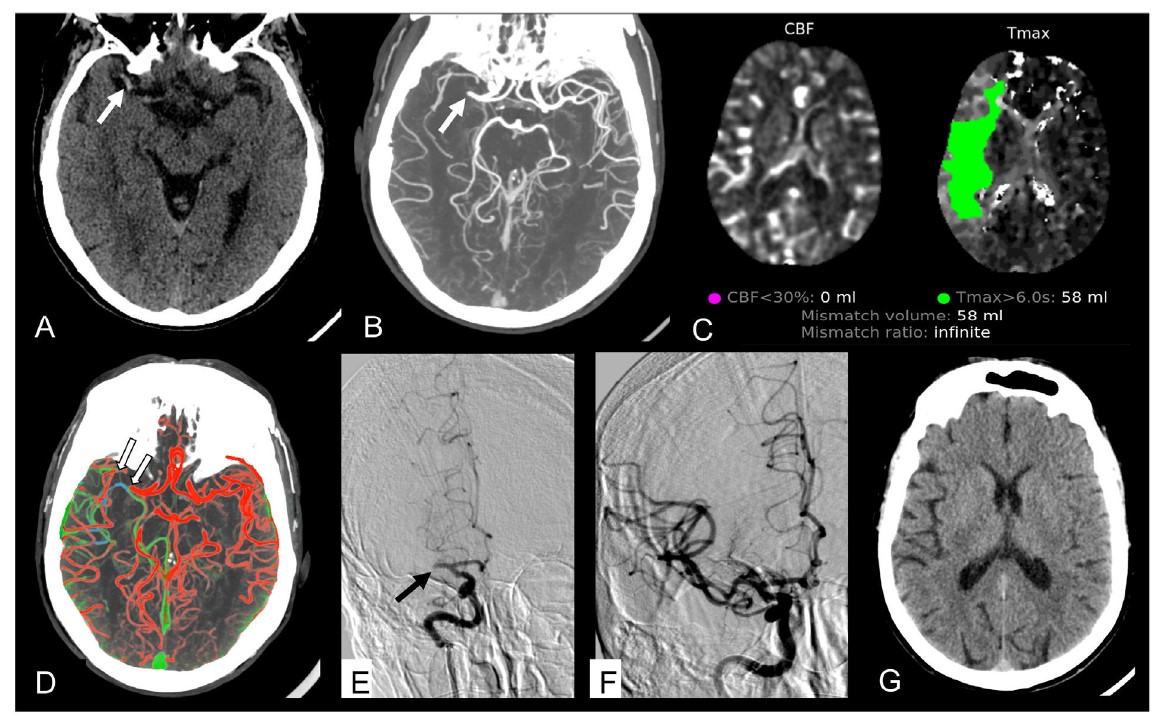

La angio-TC en el protocolo del código ictus permite la evaluación no invasiva del árbol vascular cerebral y, por tanto, detectar oclusiones, estenosis y otras anomalías vasculares en pacientes con ictus.

El artículo apunta que, en el caso de ictus hemorrágicos, la realización de una angio-TC urgente está indicada cuando las características de la hemorragia sugieran una etiología secundaria, por ejemplo, a la rotura de una malformación vascular o un aneurisma subyacente.

Angio-TC multifase y TC perfusión (TCP) aportan información sobre el estado de perfusión del tejido en riesgo cuando existe una oclusión arterial y, por lo tanto, ofrecen marcadores indirectos de la viabilidad tisular en pacientes con ictus isquémico permitiendo una aproximación a la identificación del área de penumbra. Por ello, se utilizan con el fin de identificar pacientes con ictus isquémico que se pueden beneficiar de tratamientos de reperfusión en ventanas extendidas.